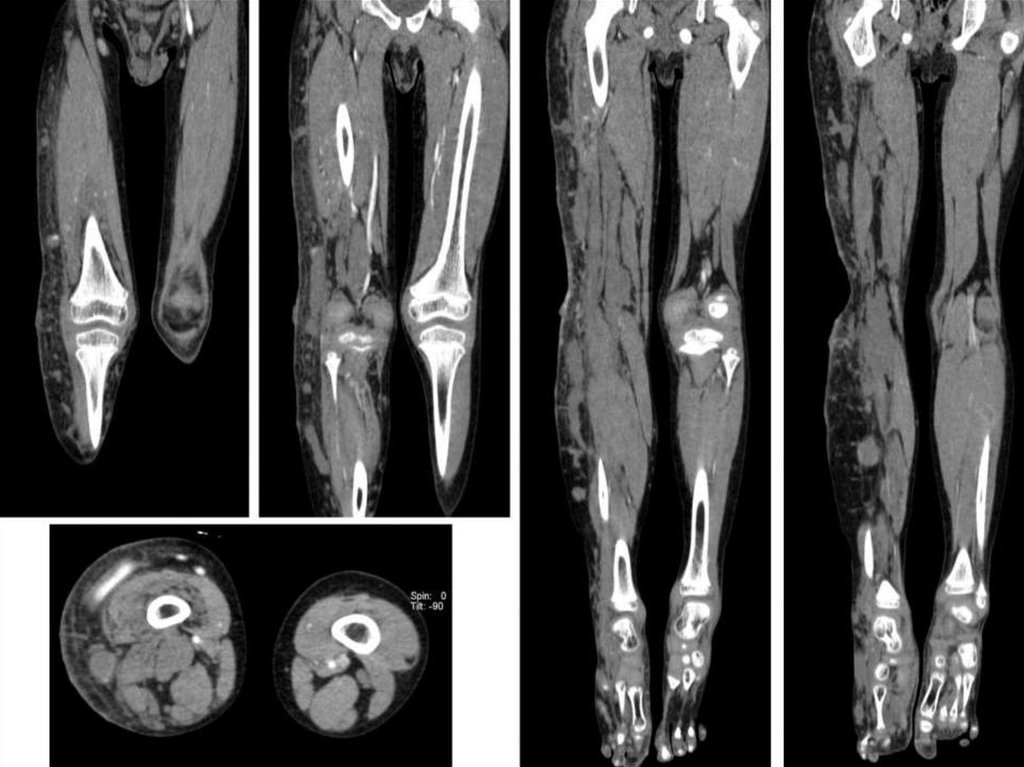

• Конечности:

1. Переломы костей;

2. Диагностика воспалительных заболеваний

костей и суставов;

3. Диагностика опухолей костей и мягких тканей

конечностей;

4. Выявление патологических изменений в

суставах и окружающих тканях при наличии

клинических признаков заболевания

(артралгии, ограничение подвижности сустава).